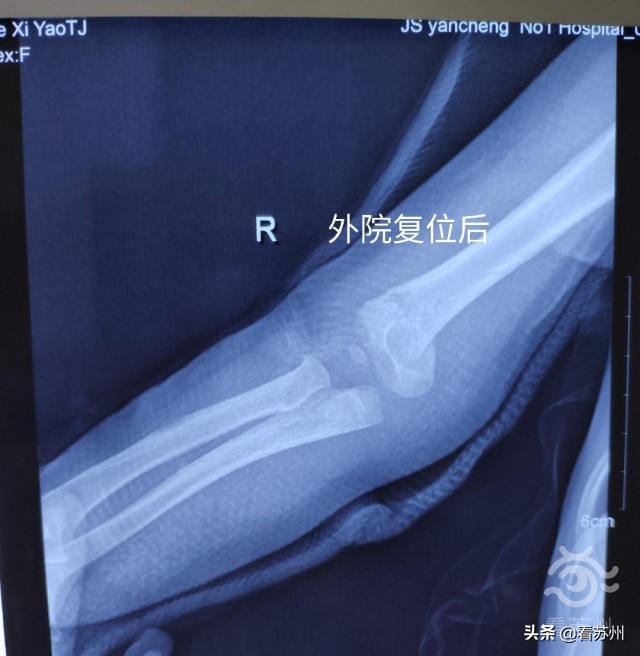

经过详细分析和评估,尤君怡认为,可采用中医传统的手法复位治疗。在常规清毒处理后,尤君怡利用吴门医派正骨法的独特技术进行了手法复位,贴上医院特制的膏药,再用木夹板固定、绷带包扎,10分钟便完成了。复查CT显示,骨折已完全复位。

“太意外了,我们做好了住院的准备,没想到几分钟就好了。”瑶瑶妈妈告诉记者,他们也是抱着试一试的心态,“都说中医慢,没想到那么快!”